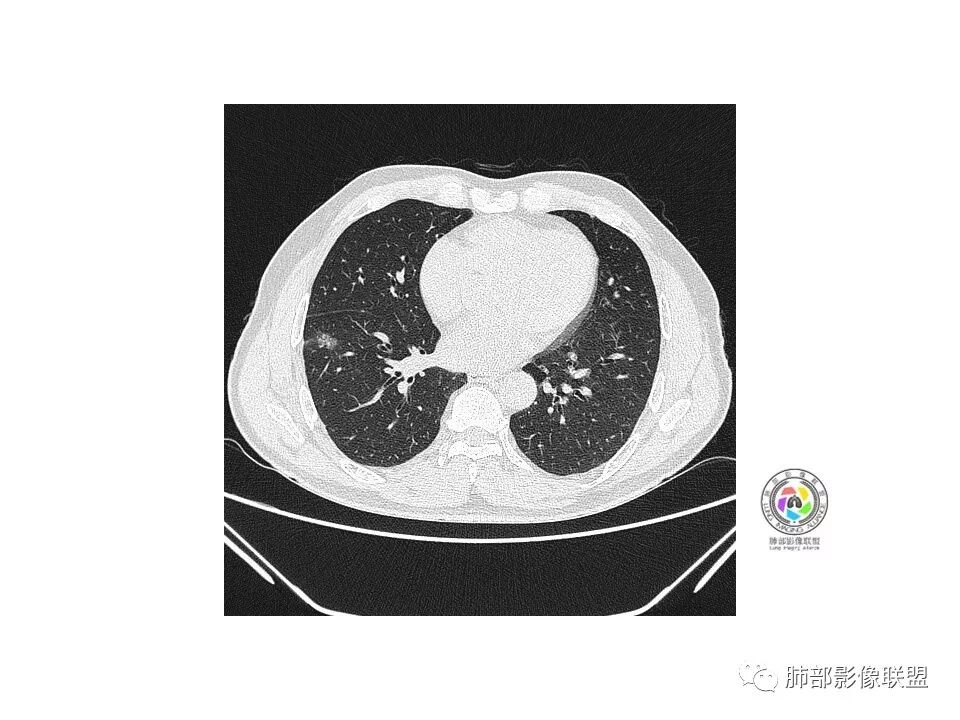

病理结果

腺癌

那AAH,AIS,MIA,IAC影像学上如何识别?那让我们一起来学习一下王兆宇老师的经典总结。

1)AAH特征小结:1.病灶呈纯磨玻璃影,无实性成分。2.病灶大小多在0.5CM以下,个别有达到1CM。3.病灶密度均较低,CT值小于-700HU。4.病灶无恶性征象。5.病灶通过长期随访不变。

2)AIS特征小结:1.病灶呈纯磨玻璃影或混合磨玻璃影,边界较清楚。2.病灶大小多在0.5CM以上,有少数可达到1.5CM以上,一般集中在0.6-1.5CM之间。3.病灶CT值在-630HU左右,临床把AAH与AIS称为浸润前病变,与浸润性病变的临界CT值约为-529HU。.少数病灶可有恶性征象,如分叶、血管集束征等。5.和AAH一样,病灶通过长期随访不变。混合磨玻璃影中的实性成分大多为血管影、肺泡塌陷、纤维灶、淋巴组织增生等原因,实践工作中要注意与癌性浸润灶区别。

3)MIA特征小结:1.病灶以混合磨玻璃影为主,少数有纯磨玻璃影,但是密度一般较高,实践工作中要注意癌性浸润灶与肺泡塌陷、血管等鉴别。典型病变表现为纯磨玻璃影中出现小于5MM的实性成分,薄扫加三维重建是诊断的关键。2.病灶大小多在1CM左右,根据我们的统计平均大小会比AIS多1-2MM左右。3.病灶CT值在-450HU左右。4.病灶可有其中的1-2个恶性征象。(分叶、脐凹征、毛刺、胸膜凹陷征、空泡征、空气支气管征等)。5.如果怀疑MIA,临床上不建议长期随访。

4)IAC特征小结:1.病变几乎呈混合磨玻璃影,罕见有纯磨玻璃影。2.病灶大小多在1CM以上。3.病灶CT值在-300HU左右,甚至更高。4.病灶1个恶性征象要怀疑诊断,2个以上者要考虑诊断。(分叶、脐凹征、毛刺、胸膜凹陷征、空泡征、空气支气管征等)。5.病理特点:以附壁样(鳞屑样)、腺泡样、乳头状、实性、微乳头状生长,其中以微乳头状生长方式最为凶险,以附壁成分生长为主者预后良好。